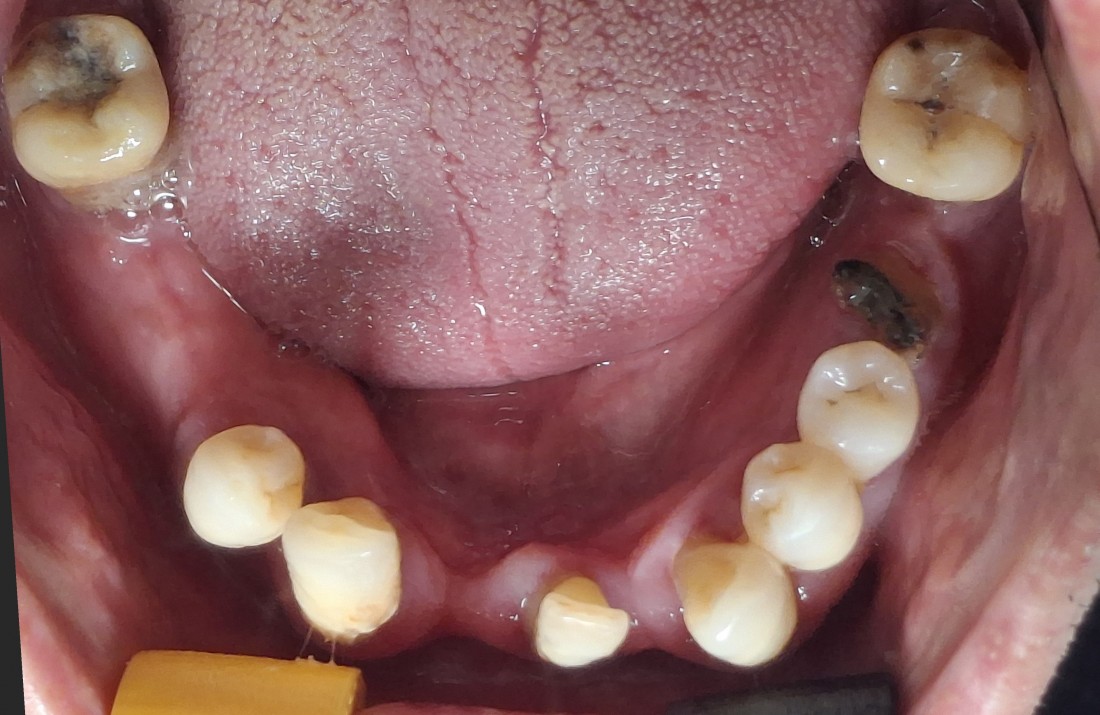

광주 전체임플란트

치료 케이스가 많은 치과가

잘하는 치과입니다.

광주 전체임플란트 케이스만

수 백가지로 정리하여

위의 홈페이지에 올려드리고 있는데요.

치과의사도 경험이 풍부한 사람이

여러 케이스를 다 다뤄보았기 때문에

좋은 임플란트 실력을 믿을 수 있습니다.